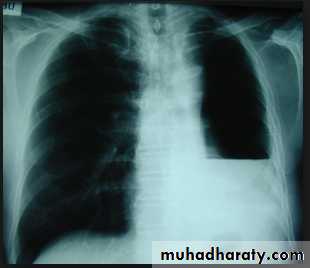

Massive pleural effusion with mediastinal shift to the left.

(A) Chest radiograph

(B) CT coronal reconstruction. A massive effusion displaces the mediastinum to the left. CT shows the important pleural effusion together with the enhanced atelectatic left lung.

Note also the depression of the right hemidiaphragm (arrows).